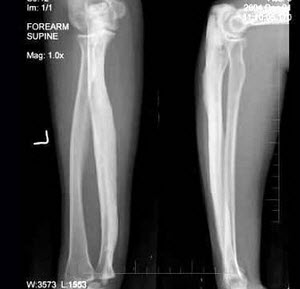

D.可有气液面

E.单侧或双侧鼻窦受累